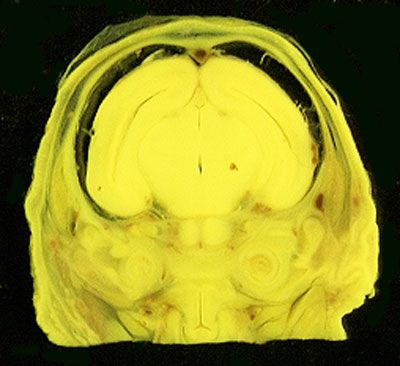

NORMAL APPEARANCE OF THE BOUIN'S FLUID FIXED RAT HEAD

The images below show the normal appearance of Bouin's fluid fixed head sections in specimens at Day 21 of gestation (day mating observed = Day 0).

It is essential that both sides of each section is examined so that structures that exist is several sections can be visualised by the examiner in 3D.

Learning objective: Compare the diagrams with your own specimens and identify all of the structures that have been labelled.

Unlabelled Images